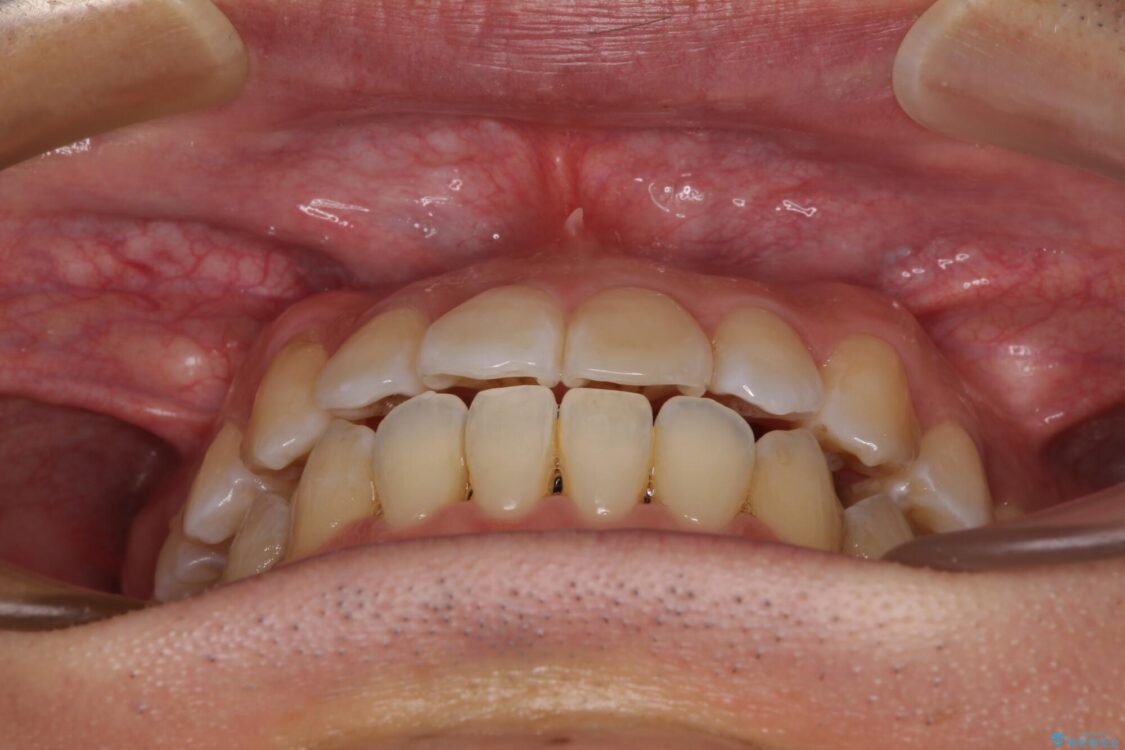

八重歯と前歯のデコボコを気にして来院された患者様です。

治療前

• 左右の八重歯が気になる ワイヤー装置での咬み合わせ改善 治療前画像